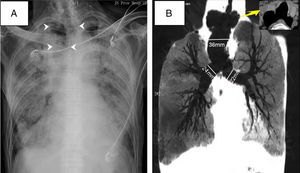

A 79-year-old man with a history of pulmonary fibrosis and Sjogren's syndrome was admitted to ICU for management of severe ARDS (Acute Respiratory Distress Syndrome) after radical prostatectomy. He presented with respiratory distress with bilateral opacities in chest radiograph (Fig. 1A). Tracheal intubation was performed the next day. However, the tidal volume continued to be instable at about 50–200ml even under fully sedation. A serious gas leakage was found as breath flow could be heard, which became better when head position fixed to the left. Taking back his history, he had had untreated tracheal abnormalities for decades. Chest computed tomography later showed diverticulum on both sides at the upper part of the trachea, and marked dilated trachea at the lower portion (Fig. 1B). Dueing to the poor attachment between the cuff of the endotracheal tube and the trachea wall, recruitment maneuvers for ARDS did not go well. The patient's condition continued to deteriorate and eventually died on the 11th day at ICU. Tracheobronchomegaly is a rare disease characterized by abnormally enlarged tracheo-bronchial tree. Chest X-ray may be misleading as it is easily overlooked on radiograph (Fig. 1A). Inexplicable poor ventilation in intubated patients should take into account the possibility of anatomic abnormalities, such as tracheobronchomegaly.